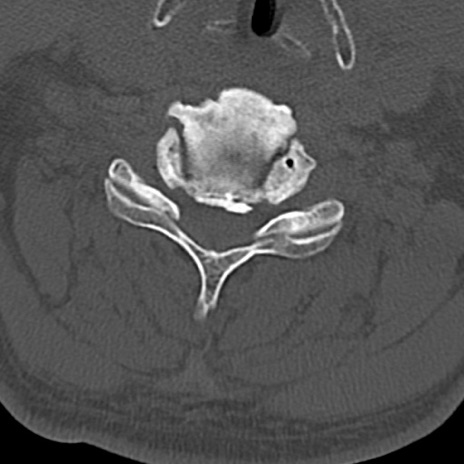

頚椎CT

横断像